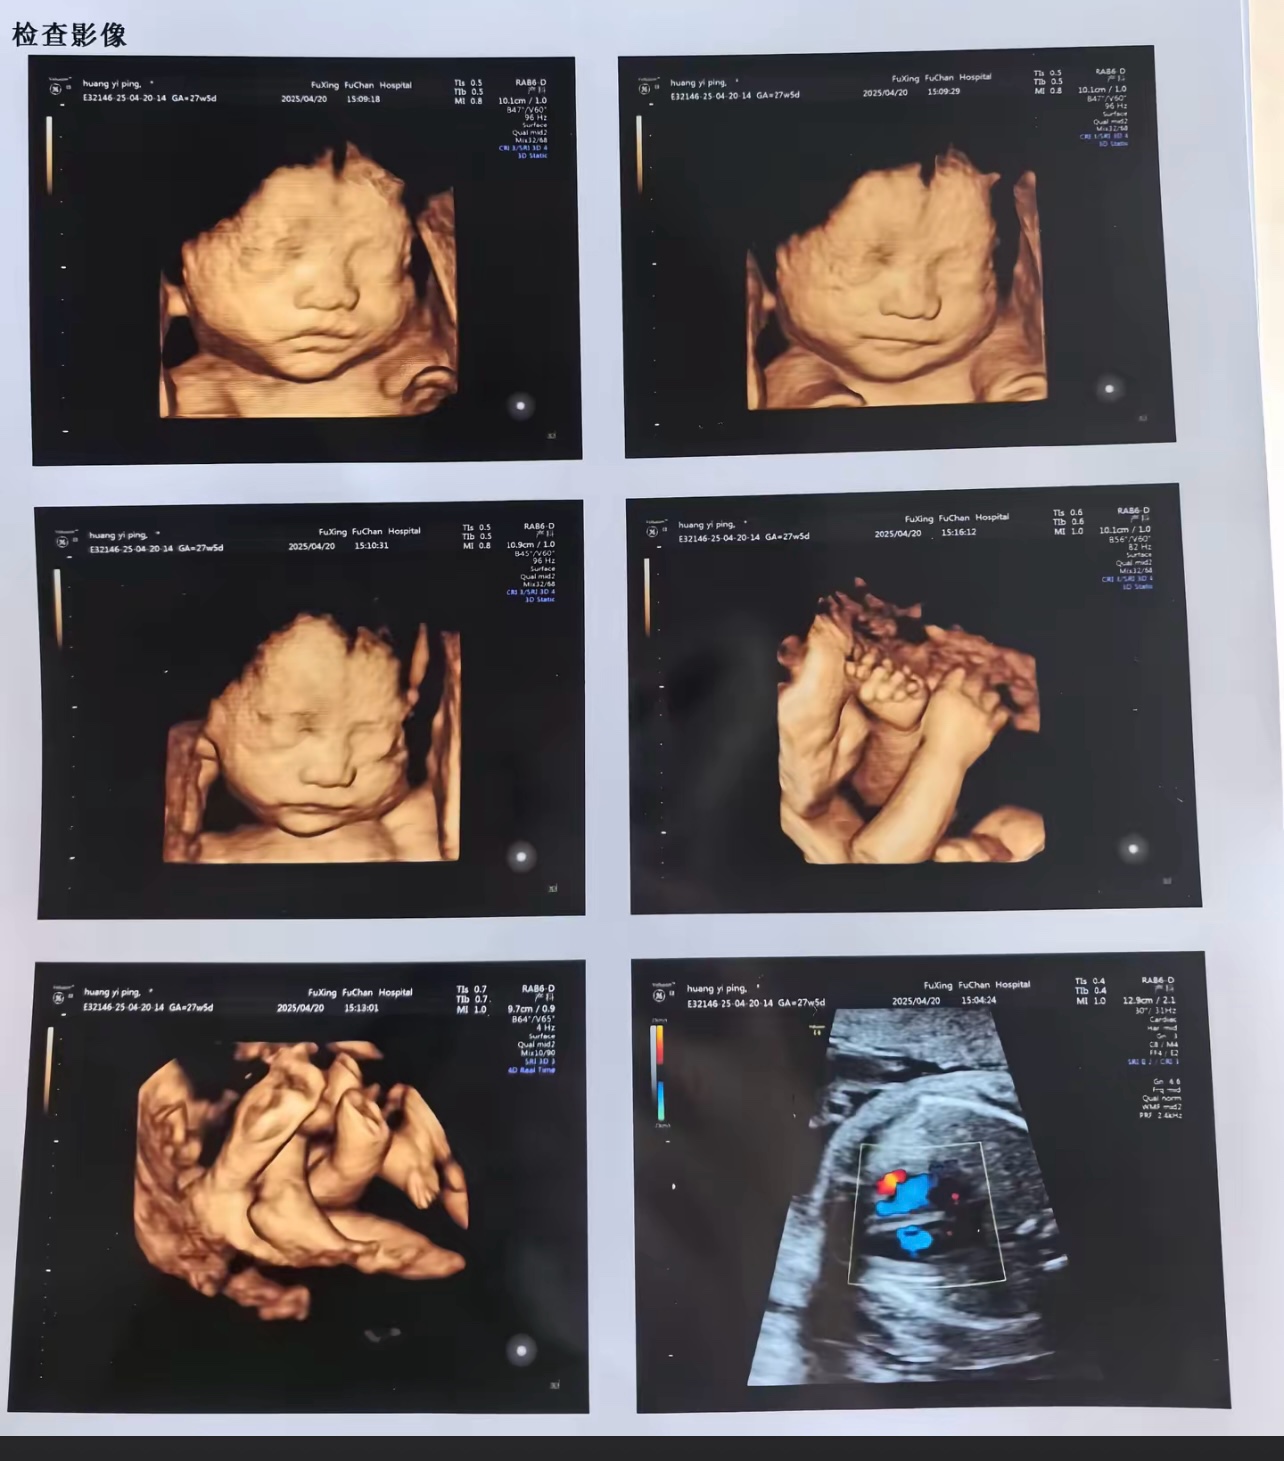

¸¾Ó×µÄÊǶþ¼¶ËÄά²Ê³¬

¿ÉÒÔ¿´µÃ¼û±¦±¦µÄÁ³Âð£¿

àÅ£¬¿ÉÒÔÅÄËÄÕÅÕÕÆ¬  ÏêÇé »Ø¸´ ·¢±íÓÚ 2025-11-8 14:10

àÅ£¬¿ÉÒÔÅÄËÄÕÅÕÕÆ¬

¿´µÄÇå³þ²»

¼Û¸ñÍüÁË£¬ÔÚ¶þ¼¶²Ê³¬µÄ»ù´¡ÉϼÓÒ»°Ù¶à

»áÓÐÕâÑùµÄÕÕÆ¬ÅÄ£¬ºÍÖ½ÖʰæµÄÂð£¿

Êǵģ¬ÎÒµ±Ê±ÊÇ»¤Ê¿ÄÃÎÒÊÖ»ú°ïÎÒÅĵģ¬ÅÄÁËËÄÕÅ  ÏêÇé »Ø¸´ ·¢±íÓÚ 2025-11-11 13:48

Êǵģ¬ÎÒµ±Ê±ÊÇ»¤Ê¿ÄÃÎÒÊÖ»ú°ïÎÒÅĵģ¬ÅÄÁËËÄÕÅ

ÄǾͿÉÒÔÁËÓÐÕâÑùµÄÒ²¿´µÃÇå³þ±¦±¦×ì°ÍÎå¹ÙÁË£¬ÎÒ±¾À´»¹Ëµ´òËãÈ¥ÎäÒÄɽ¶þÔº×öËÄά

ÏÖÔÚ¿´À´²»ÓÃÁË